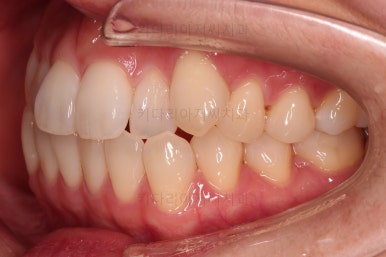

1. 초진

초진 시 입안의 모습입니다.

덧니가 눈에 띄고요.

맞물림이 긴밀하지 못한 상태였습니다.

전반적으로 약간 삐뚤지만 많이 심하다고 보긴 힘들었습니다.